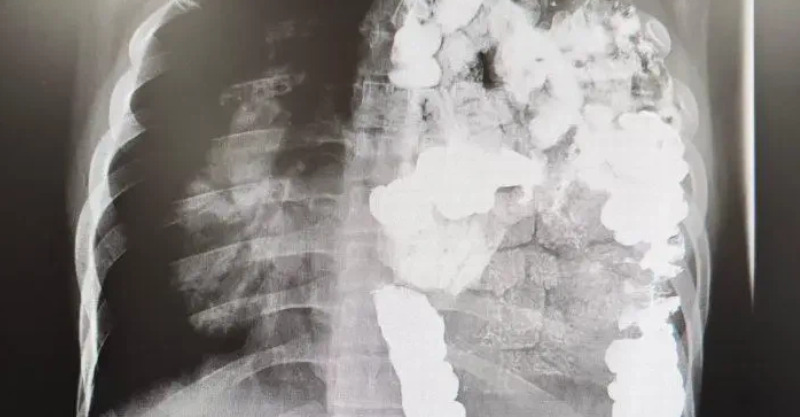

4.防癌抗癌:香蔥所含果膠,可明顯地減少結腸癌的發生,有抗癌作用,蔥內的蒜辣素也可以抑制癌細胞的生長。